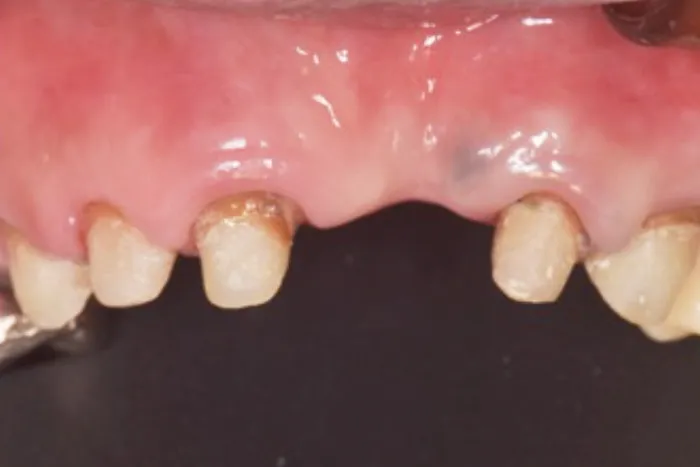

症例② 前歯が一本だけ長いのが気になる

Before

After

| 主訴 | 前歯が一本だけ長いのが気になる |

|---|---|

| 治療期間 | 8ヶ月 |

| 治療費 | 結合組織移植術 77,000円 ※保健治療の金額は含みません |

| 治療内容 | 根管治療・結合組織移植術・レジン前装冠 |

| 治療のリスク | 術後の腫脹・出血 / 歯肉退縮による金属色の露出 |

▲治療のコメント

歯を抜いて歯茎が退縮してしまったことが原因で歯が長くなっていました。なので、上顎口蓋から結合組織を移植することで退縮した歯肉を再建しました。その上でブリッジのやり直しを行いました。